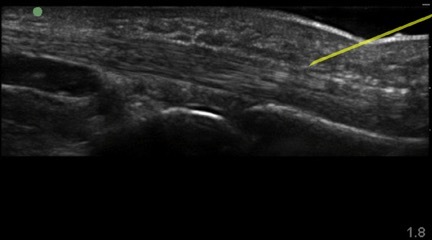

Hand Flexor Tendon 2 Image